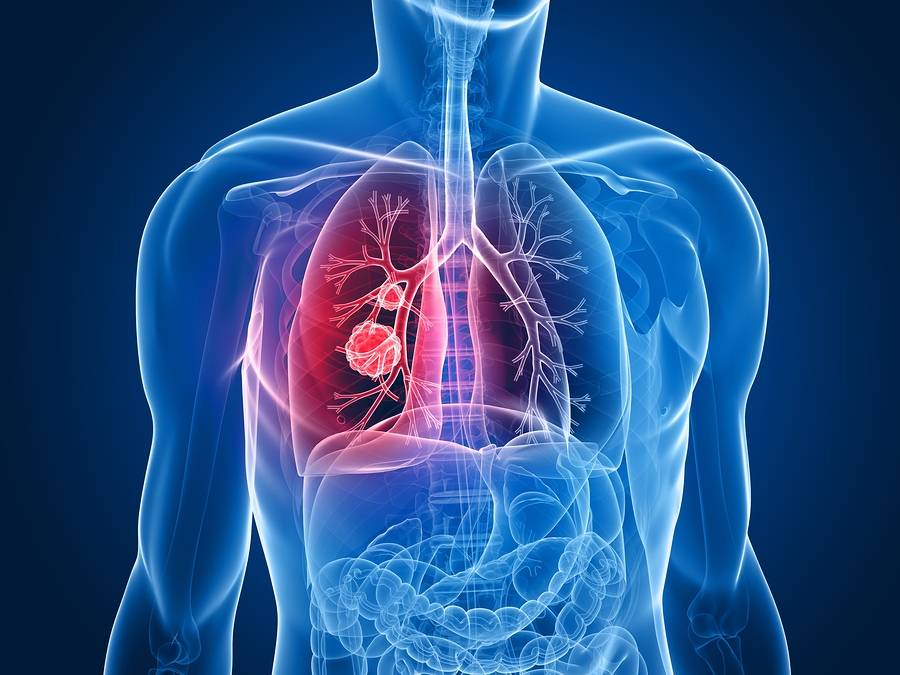

Asbestos lung cancer is a type of cancer that develops in the lung tissues due to the inhalation of asbestos fibers. These fibers can cause inflammation, scarring, and genetic damage to the cells in the lungs, leading to cancer over time. Asbestos lung cancer can take decades to develop after initial exposure, making early detection challenging.